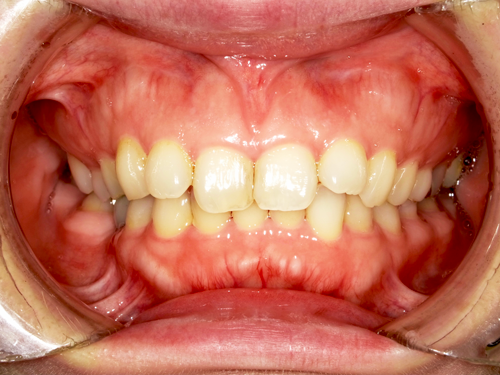

インプラントは、審美性の高い素材を使用でき、自然な仕上がりを実現可能です。ほり歯科・矯正歯科中央林間では、精密性の高い治療により、より美しい仕上がりを目指しています。